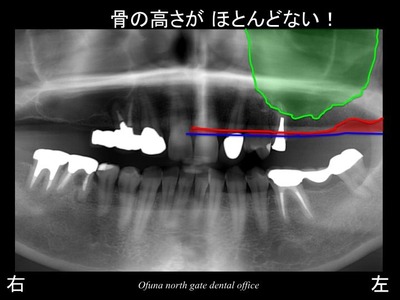

今回治療を行う部位は上顎左側です。

上顎左側の奥歯が2歯分欠損しています。

いつものように 骨吸収の状態を分かりやすくするために

骨吸収の状態を線で書いたのが以下のレントゲンになります。

青線が骨吸収を起こす前の骨の位置です。

赤線は、現在の骨の位置です。

さらに わかりやすくするために、骨吸収部位を赤色で表示します。

次に上顎洞という空洞を見てみましょう!

以下のレントゲンの緑線は上顎洞という空洞です。

骨ではなく、穴が開いているのです。

さらに分かりやすくするために

上顎洞を緑色で塗ってみましょう!

骨の高さが非常に少なくなっているのが分かるかと思います。

このままであるとインプラント治療は難しくなります。

短いインプラントしか埋入するこができません。

短いインプラントの予後は明らかに悪いのです。

しかし、今回の症例では、4〜5ミリ程度の骨の高さしか存在していません。